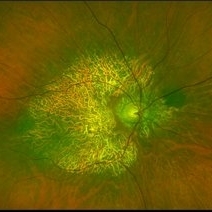

Not All Stars Are in the Sky — Some Live in the Eyes of Those Learning to See in New Ways

Not All Stars Are in the Sky — Some Live in the Eyes of Those Learning to See in New Ways

Apr 21 2025 by rohan jain

Stargardt disease

Photographer: Dr. ROHAN JAIN

Condition/keywords: fleck retinopathy, fundus autofluorescence (FAF), hereditary macular dystrophy